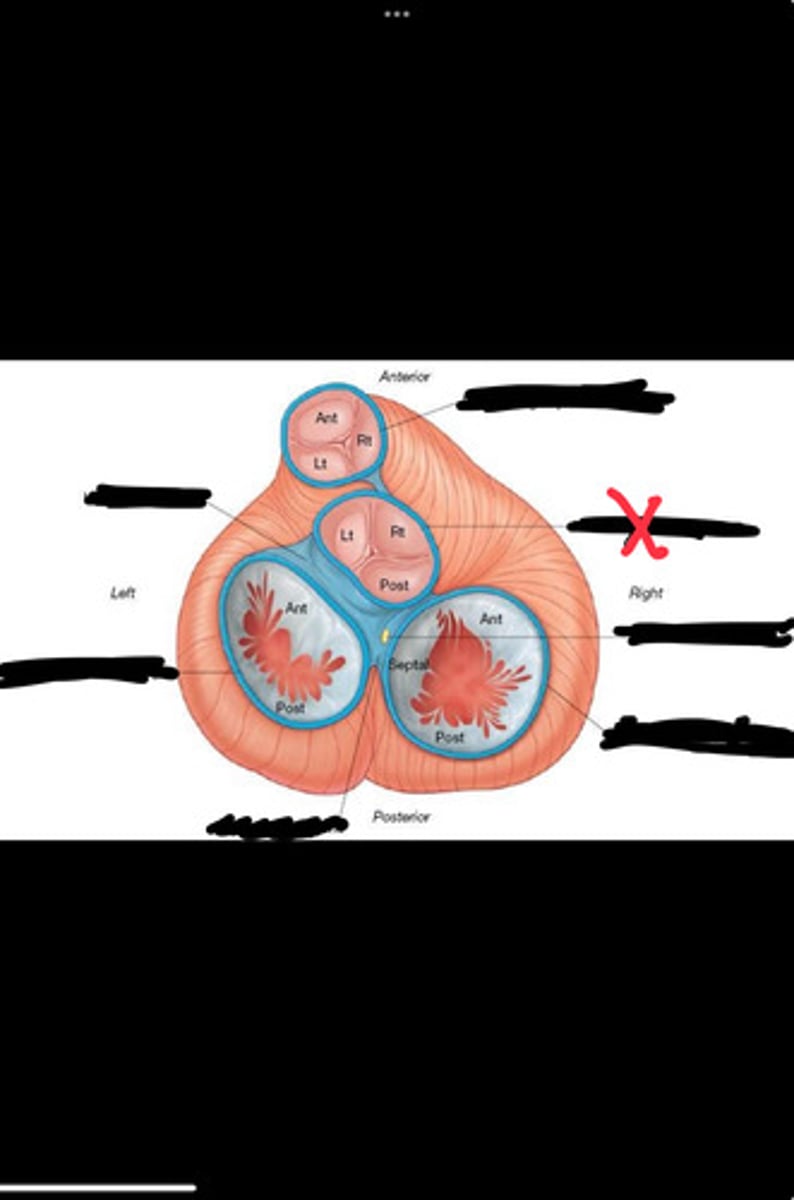

Right fibrous trigone

Left fibrous trigone

Fibrous ring of pulmonary valve

Fibrous ring of aortic valve

Atrioventricular bundle

Right atrioventricular ring

Left atrioventricular ring